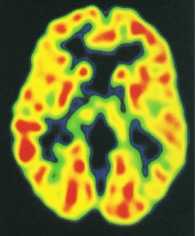

这是一张10月大婴儿的大脑图,10个月大婴儿的新陈代谢就已经达成人的水平,还继续增长,一直到5岁时,达到成人的2.5倍,然后慢慢下降。

所以1-5岁是孩子记忆发展的第一个高峰时期和关键期。0-3岁的孩子对鲜明、生动、有趣、形象直观的事物,生动形象的词汇,有强烈情绪体验的事物,多种感官参与的事物容易记忆,也容易保存下来,尤其在1岁以后随着语言的发展孩子的记忆力逐渐增强,长时记忆开始发育。